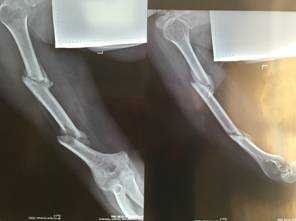

На операции: в области обеих бедренных костей определяются костные мозоли с патологическим разрастанием фиброзной ткани. Определяется незначительная подвижность костных отломков. Выполнена остеотомия бедренных костей на уровне костной мозоли, удалена фиброзная ткань (Рис. 3). С помощью разверток произведено вскрытие костно - мозгового канала в проксимальных и дистальных отломках. Произведена репозиция отломков и фиксация интрамедуллярными универсальными бедренными штифтами Aesculap. Дистальные блокирующие винты установлены в динамические отверстия (Рис. 4). Разница в длине нижних конечностей устранена. Выполнено послойное ушивание послеоперационных ран отдельными узловыми швами. Асептические повязки. Кровопотеря составила 300 мл.

Рис.3. Интраоперационные фотографии